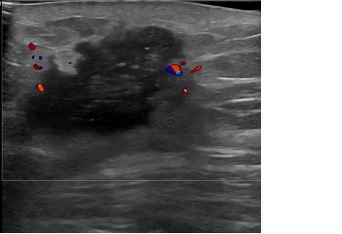

상기환자는 외부건진이상소견정밀검사위해  내원하신 60대중반

여성분으로 의심스러운 좌측혹 조직검사 시행해 유방암 진단되었습니다.